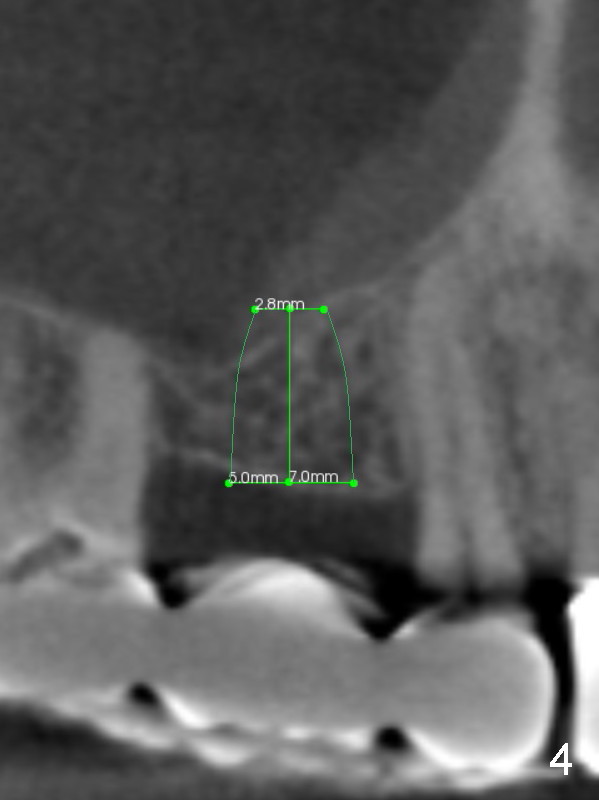

A 63-year-old man complains of loose bridge in the upper right quadrant. There is open margin at #4 (Fig.1). After sectioning between #2 and 3 without anesthesia, explore the tooth/abutment of #4 for caries. Build up or Cavit will be placed for splinted provisional with implant at #3. Use Magic Split for access and initial bone expansion, followed by Magic Expanders until 4.3 mm one. Bone density is 100-500 units. The depth starts with 7 mm and finishes with 9 mm or more from gingival margin (Fig.2). CBCT coronal section shows the bone width 8.6 mm (Fig.3). Place a 4.5x9 mm dummy implant at the gingival level for depth determination. Use a definitive implant 1-2 sizes larger (Fig.4,5). Draw blood for PRF. Also prepare Magic Lift Kit and DIO one.